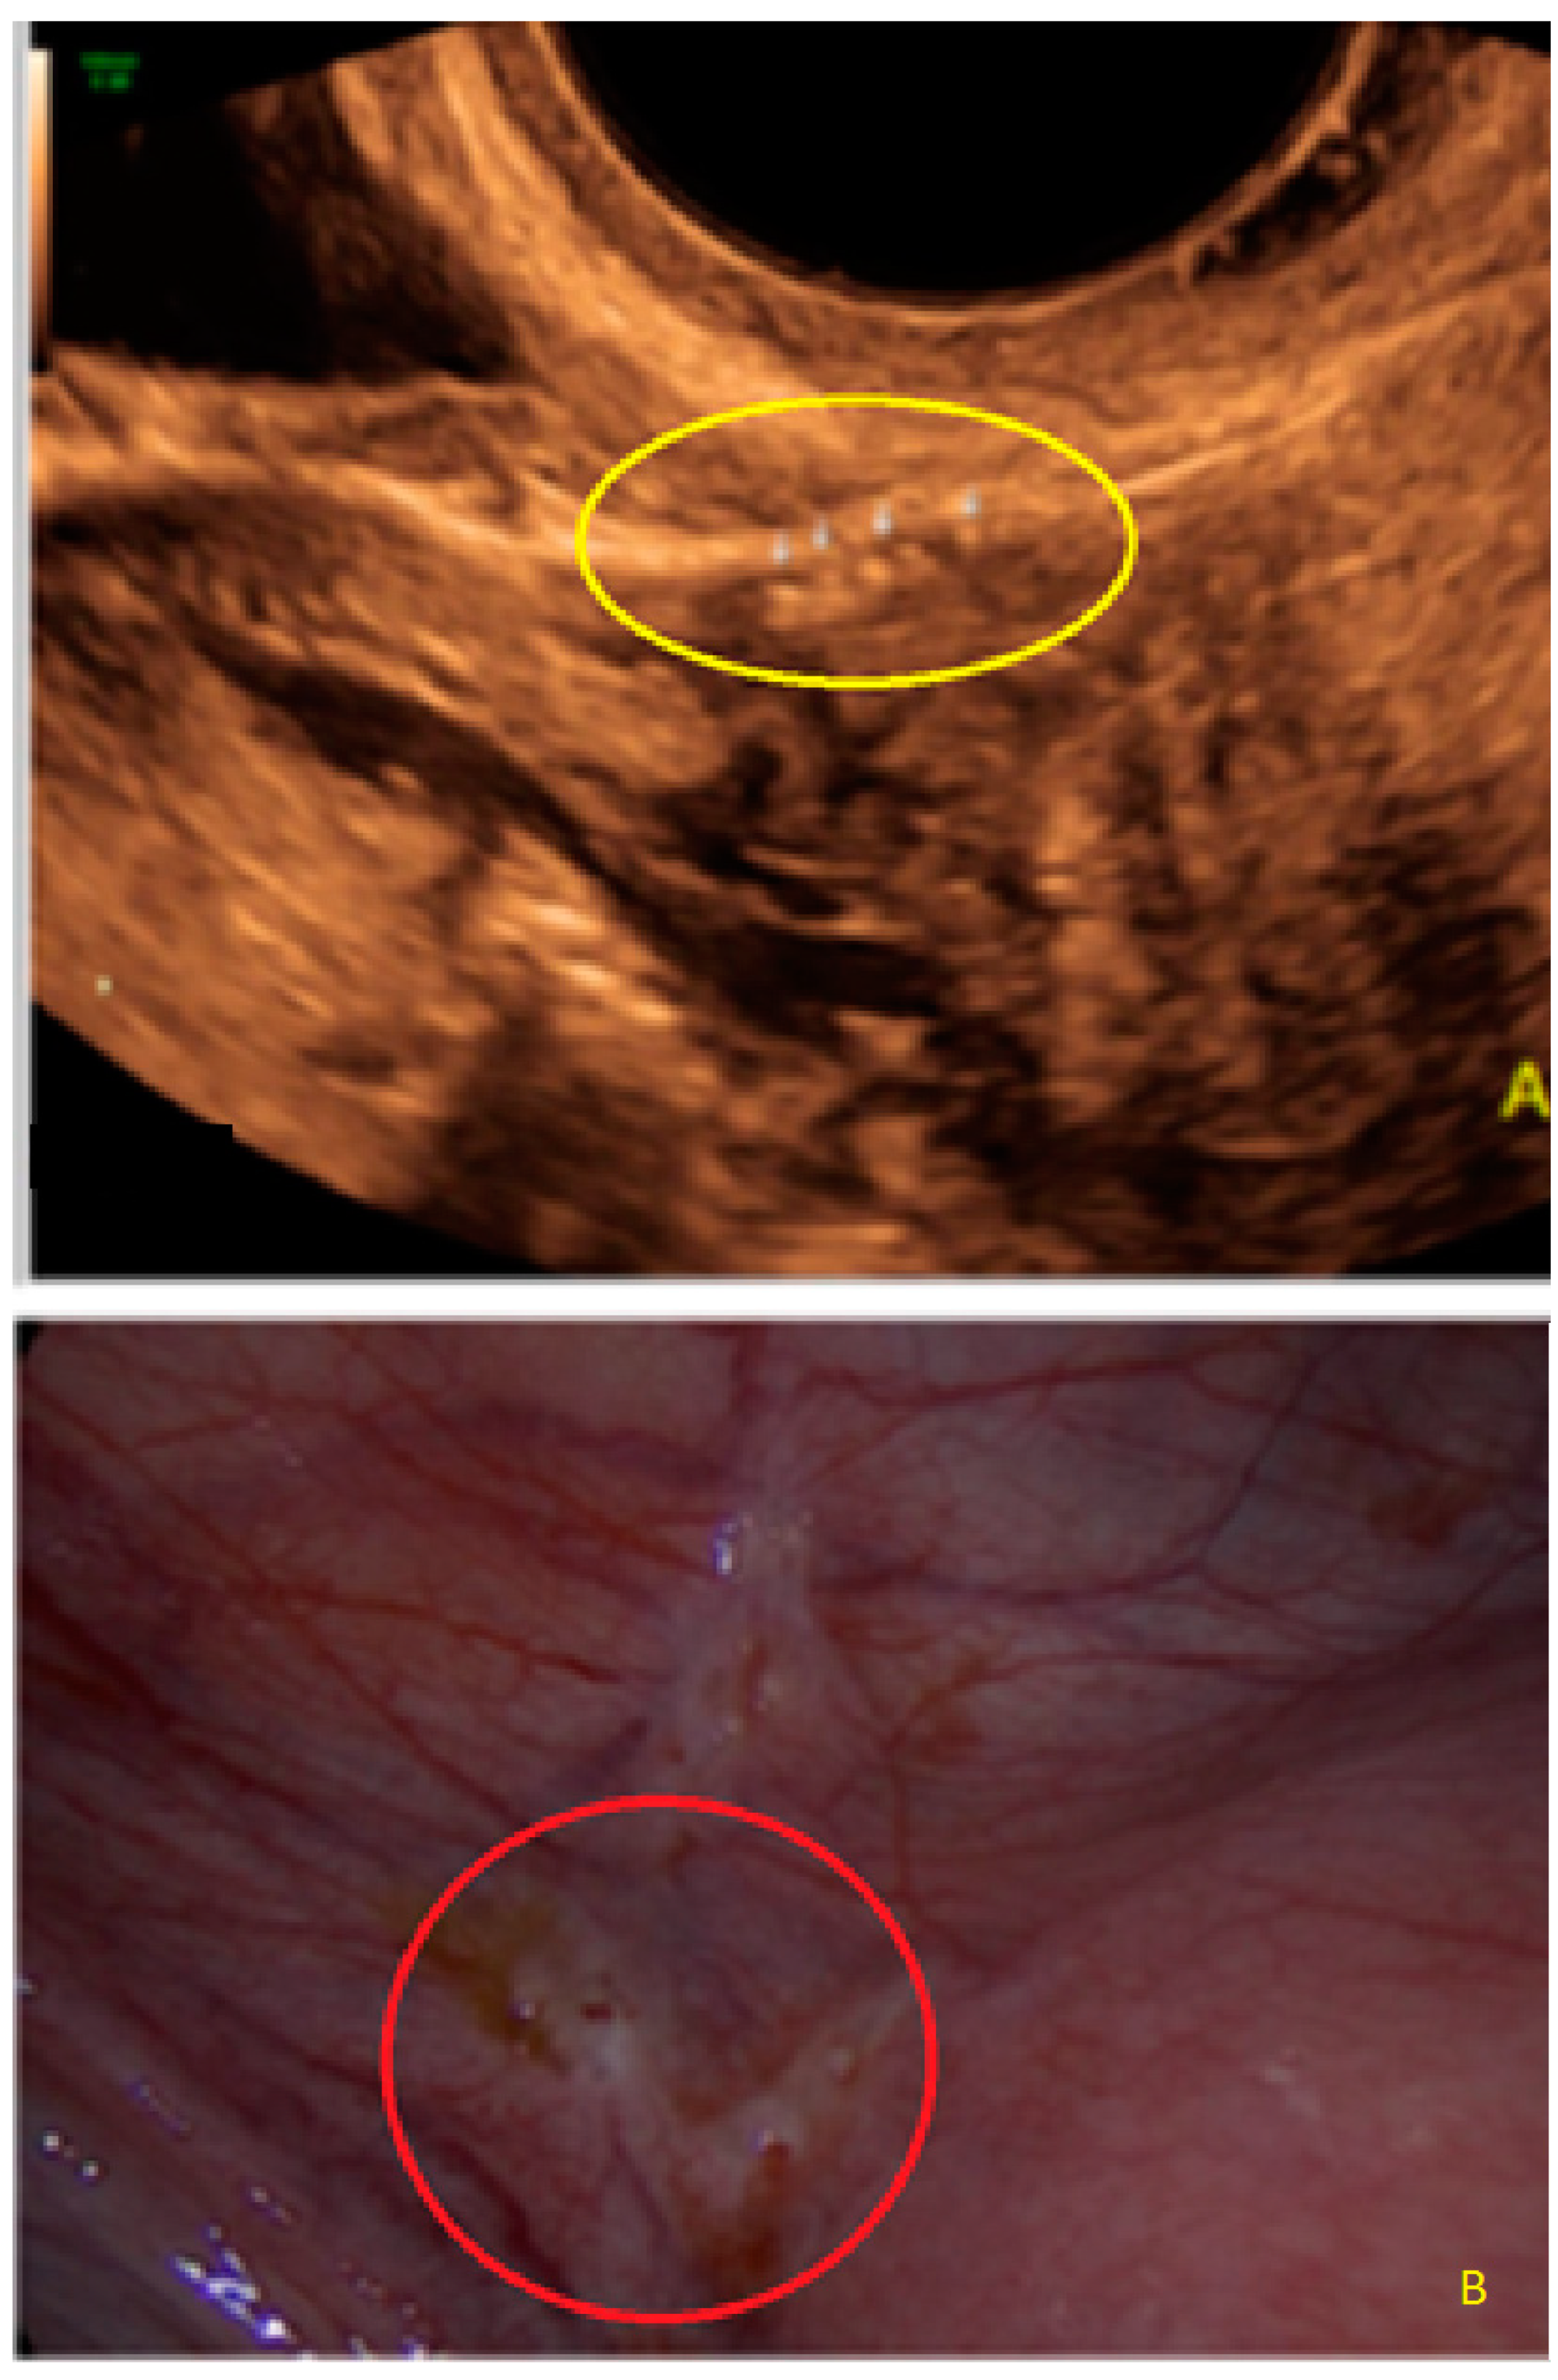

- The presence of hyperechoic foci (we called this a “pearl”).

- The presence of velamentous (filmy) adhesions associated to the lesion (we called this a “veil”).